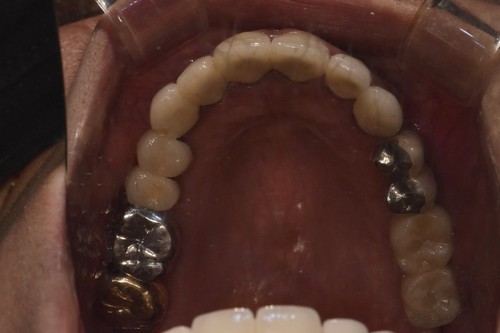

임플란트를 식립한 후에는 통상적으로는 3개월 후에 임플란트 보철물이 들어가는데 환자분의 사정으로 치과 내원을 못 하셔서 약 5개월 후에 오셨는데 왼쪽 아래 치아의 뿌리 부위의 충치가 발견되어서 아래 치아는 발치하면서 식립하는 즉시식립을 해 드렸습니다.

보통 하악에 임플란트 식립하면 2개월 이내에 치아가 들어가는데 마찬가지로 환자분 사정으로 못 오시다가 6개월이 지나서야 위,아래 임플란트 머리가 들어가고 마무리 할수 있었습니다.